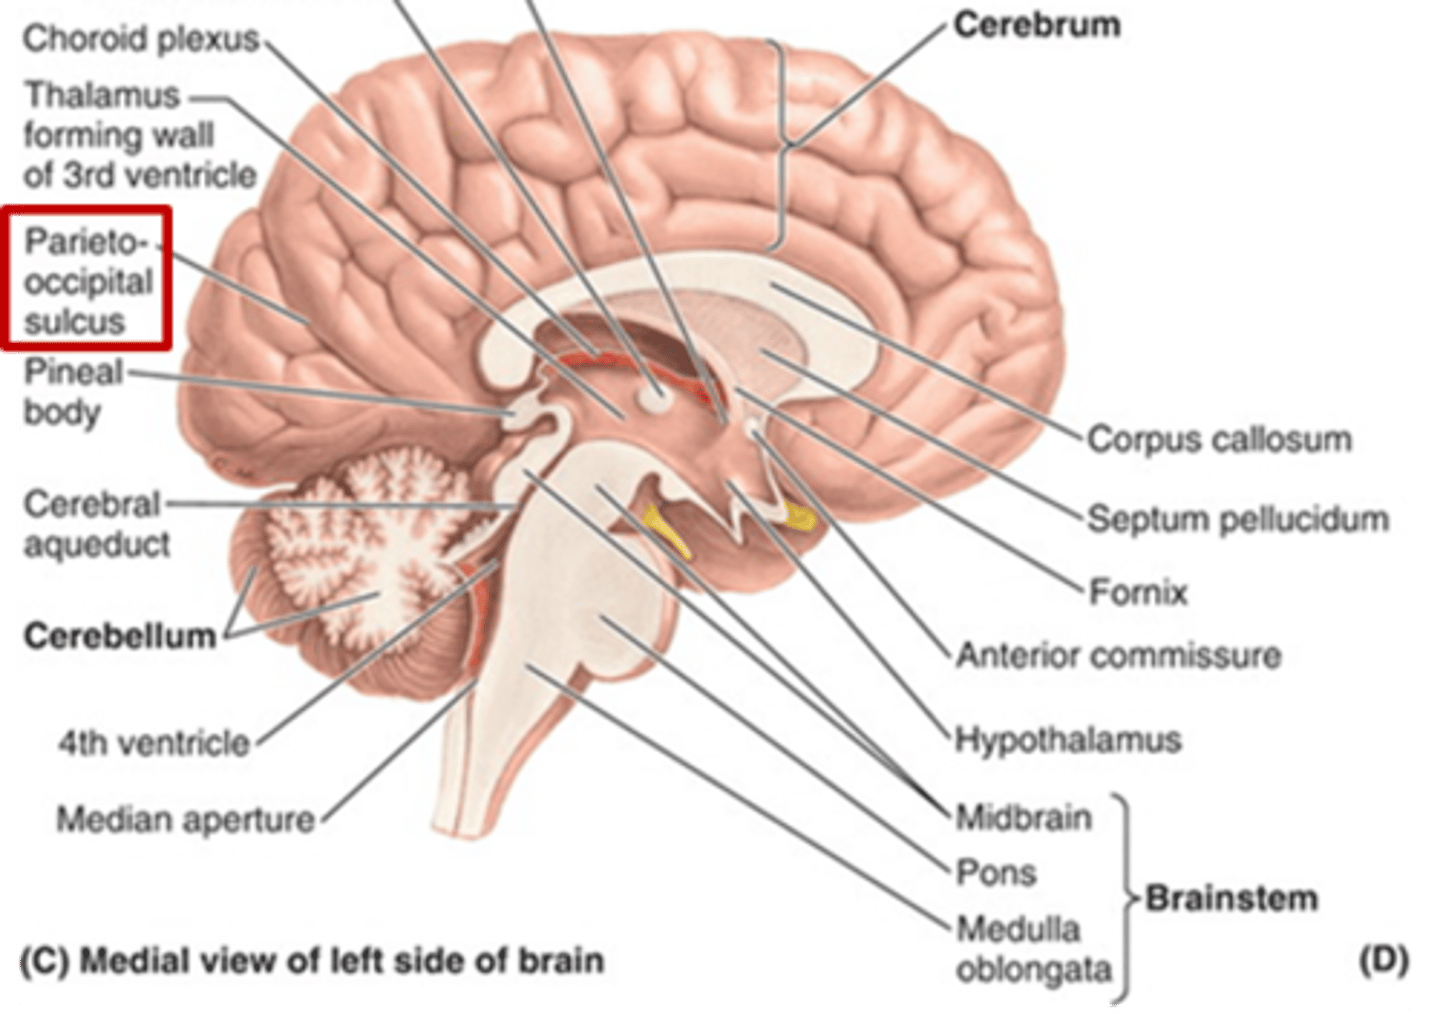

which sulcus separates the parietal lobe from the occipital lobe?

parieto-occipital sulcus

what are 3 key white matter structures found in the cerebrum?

1. corpus callosum

2. corona radiata

3. internal capsule

what cerebral white matter structure is a large bundle of nerve fibers that connects the left and right cerebral hemispheres, allowing them to communicate?

corpus callosum

what is the fan-shaped cerebral white matter sheet that is continuous ventrally with the internal capsule?

corona radiata

what cerebral white matter structure is a tract that carries sensory and motor information to and from the cerebral cortex?

internal capsule

what are 2 important structures of the diencephalon?

1. thalamus

2. hypothalamus

what structure of the diencephalon regulates the of flow sensory and motor information from various location that will ultimately reach the cortex?

thalamus

what structure of the diencephalon is the relay station for all but one sensory tracts on their way to the cortex? what is the exception?

thalamus

olfactory is the only tract to bypass the thalamus and go directly to the cortex

what structure of the diencephalon is the main visceral control center of the brain?

hypothalamus

what structure of the diencephalon mediates a wide range of functions through connections with endocrine, autonomic, somatic motor, limbic systems, and maintaining a state of homeostasis?

hypothalamus

what are the 3 parts of the brainstem?

1. midbrain

2. pons

3. medulla

which region of the brainstem contains the cerebral aqueduct?

midbrain

looks like a hole in the center of the midbrain

cerebral aqueduct connects the 3rd and 4th ventricles